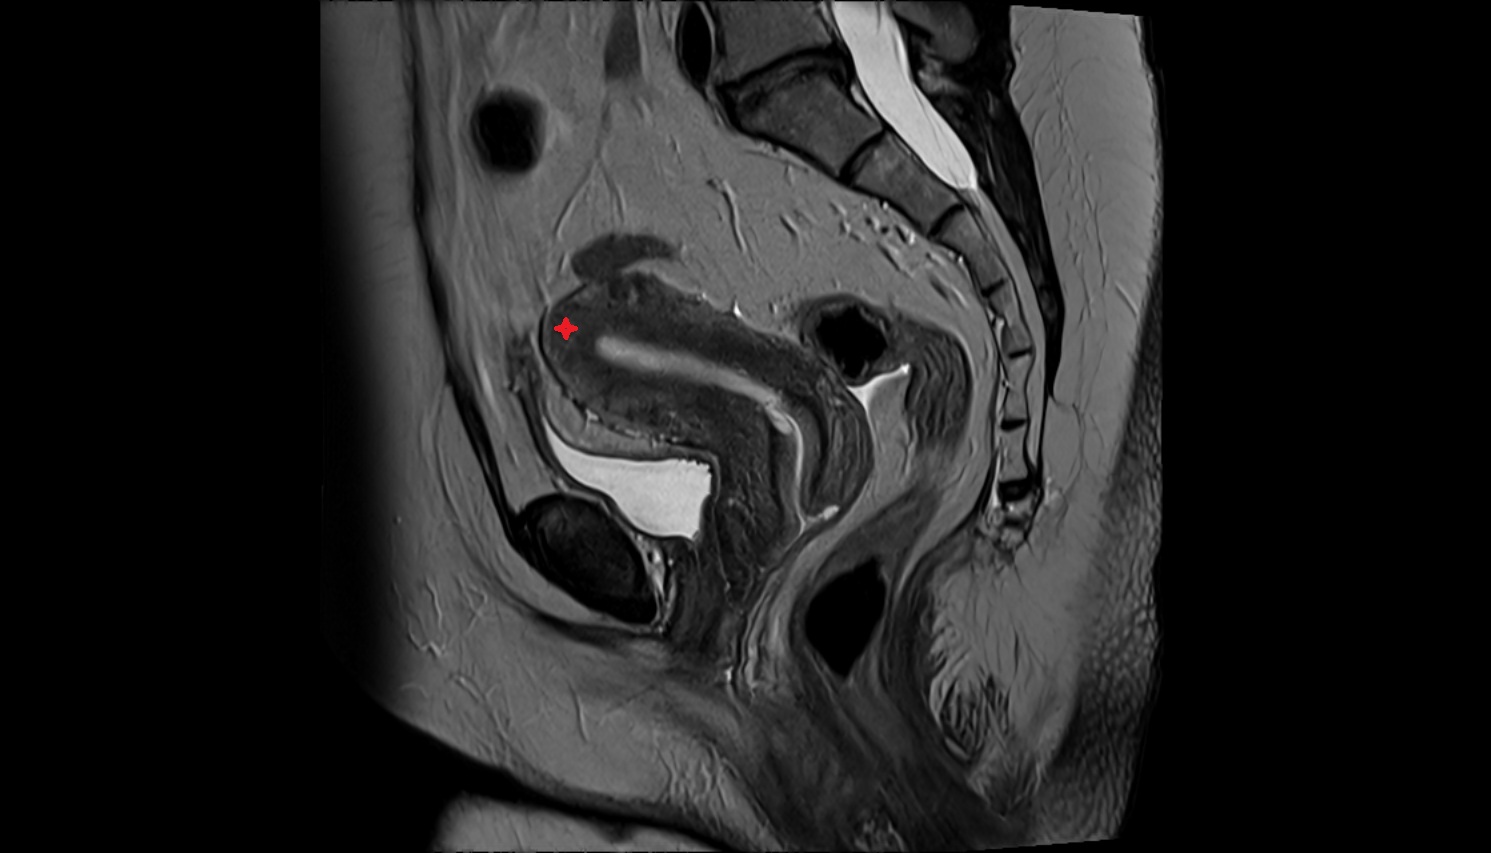

- Uterus

- Body of uterus

- Fundus of uterus

- Cervix of uterus

- Isthmus of uterus

- Vagina

- Fornix of the vagina

- Endometrium of uterus

- Myometrium of uterus

- Perimetrium of uterus

- Junctional zone of uterus

- Vesicouterine pouch

- Rectouterine pouch (pouch of Douglas)